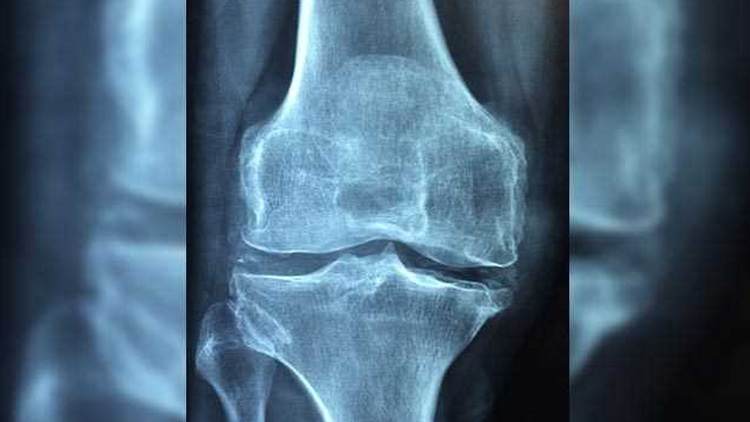

രോഗങ്ങളിൽനിന്നുതന്നെ പലപ്പോഴും രോഗസാധ്യത സംശയിക്കാനാകും. ചില സാധാരണ പരിശോധനകൾ, തൈറോയ്ഡ് പരിശോധന, രക്തത്തിലെ കാൽസ്യം, ജീവകം -ഡി ഇവയുടെ അളവുകൾ കൂടാതെ ‘എക്സ് റേ’ പരിശോധനയുമാണ് സാധാരണ ആദ്യം ചെയ്യുക. അസ്ഥിക്ഷയത്തെപ്പറ്റി കൂടുതൽ വിവരങ്ങൾ വേണെമങ്കിൽ ബോൺ മിനറൽ ഡെൻസിറ്റി ടെസ്റ്റ് (ബി.എം.ഡി), ഡ്യുവൽ എനർജി എക്സ്റേ (ഡി.എക്സ്.എ) മുതലായ പരിശോധനകൾ വേണ്ടിവന്നേക്കാം.